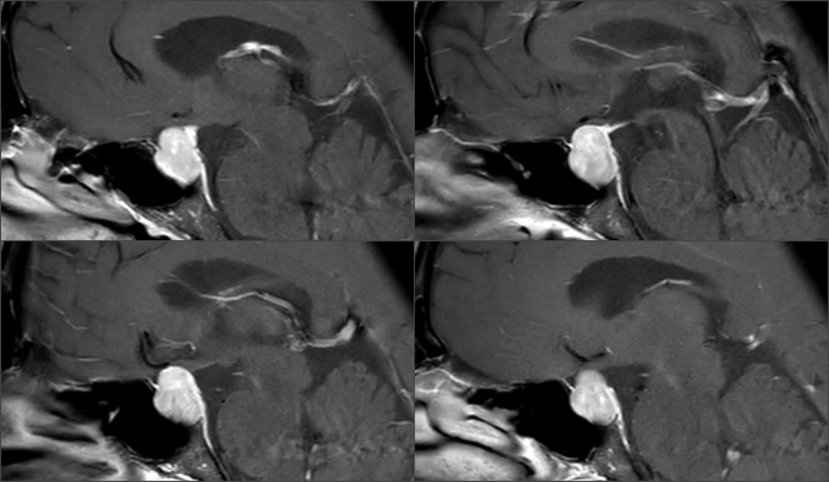

影像资料

Knosp1级肿瘤,鞍隔被肿瘤推挤向上,冠状位略呈“雪人征”,术中鞍隔可能塌陷 T2信号较为均质,考虑肿瘤有一定韧性 垂体柄偏向左侧,残存垂体左侧更多,鞍隔面、鞍底面亦有薄层受压垂体组织,术中需注意保护,亦有助于辨认肿瘤与垂体之间的分界面

术前术后影像学对比